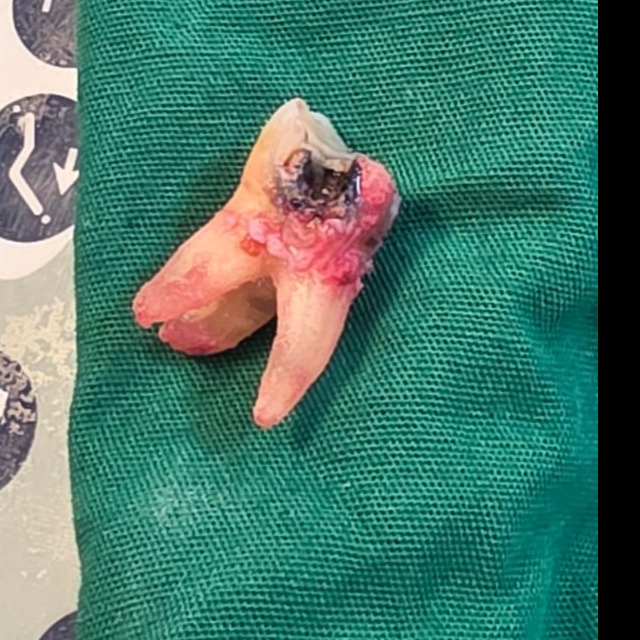

• Severe tooth decay beyond repair

• Infection that cannot be treated with root canal

• Broken or fractured tooth

3. Tooth Removal

Surgical Extraction

• Required for broken or impacted teeth

• May involve a small incision